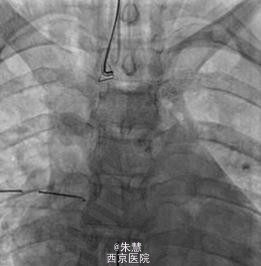

起初尝试使用支气管镜取出异物没有成功,并且还造成右侧张力性气胸,进而给予胸腔闭式引流进行治疗。由于订书钉经常从血管钳上滑落,采用微型捕捞器将其固定在支气管导管的远端。之后将支气管导管、引导导管、捕捞器、订书钉一起取出,取出的过程中,订书钉的尖端朝里,以防止声带被异物损伤。透视介导的时间长度一共是22分钟。患者术后未出现并发症,并于第二天出院。